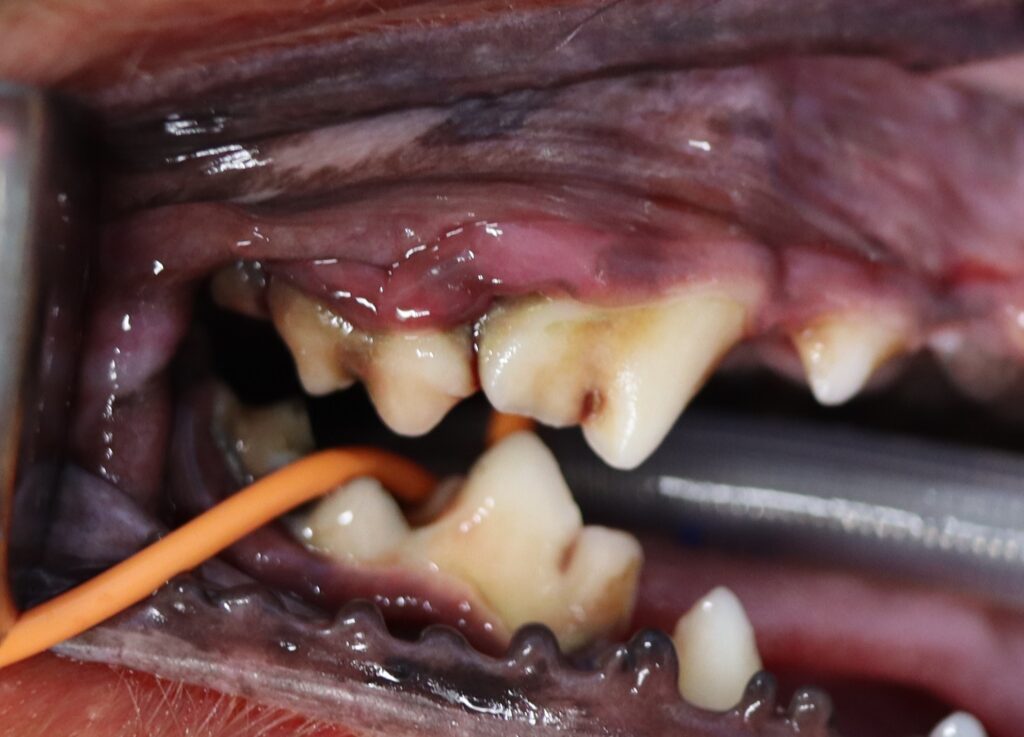

今回は小型犬に多い「上顎第二後臼歯(じょうがく・だいにこうきゅうし)」の歯周病について解説します。

この歯は口の奥にあり、気づかれにくい部位ですが、歯周病リスクが非常に高い歯です。

とくにトイプードル・チワワ・ポメラニアン・ヨークシャーテリアなどの小型犬では、顎が小さいために歯の間が狭く、歯石や歯垢が溜まりやすい歯でもあります。

上顎第二後臼歯に多い歯周病の症状

この歯の歯周病は、進行してから気づかれることが多いのが特徴です。

- 歯ぐきの赤み・腫れ

- 口臭の悪化

- 食べにくそうにする(特にドライフード)

- よだれや出血

- 目の下の腫れ(重度の場合:歯根膿瘍や外歯瘻)